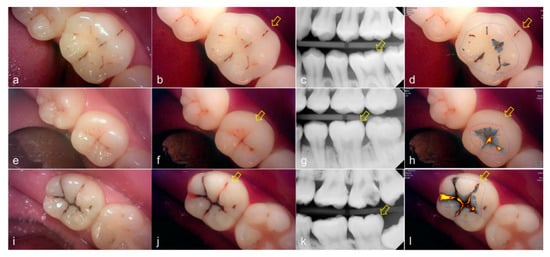

Representative images of QLF and bitewing radiograph of occlusal dental caries are shown in Figure 4 and Figure 5.

Figure 4.

Occlusal dental caries: (a–d) QLF caries score 1 (fluorescence loss and red fluorescence present as a line or spot in pits and/or fissures) and radiographic caries score 0 (no radiolucency visible) on #36; (e–h) QLF caries score 2 (fluorescence loss and red fluorescence glow extending around pits and fissures) and radiographic caries score 0 (no radiolucency visible) on #36; (i–l) QLF caries score 3 (red fluorescence glow extending around pits and fissures and a dark shadow from dentin present) and radiographic caries score 0 (no radiolucency visible) on #37; (a,e,i): white-light image of QLF; (b,f,j): fluorescence image of QLF; (c,g,k): bitewing radiograph; (d,h,l): analyzed QLF image using QA2 software.